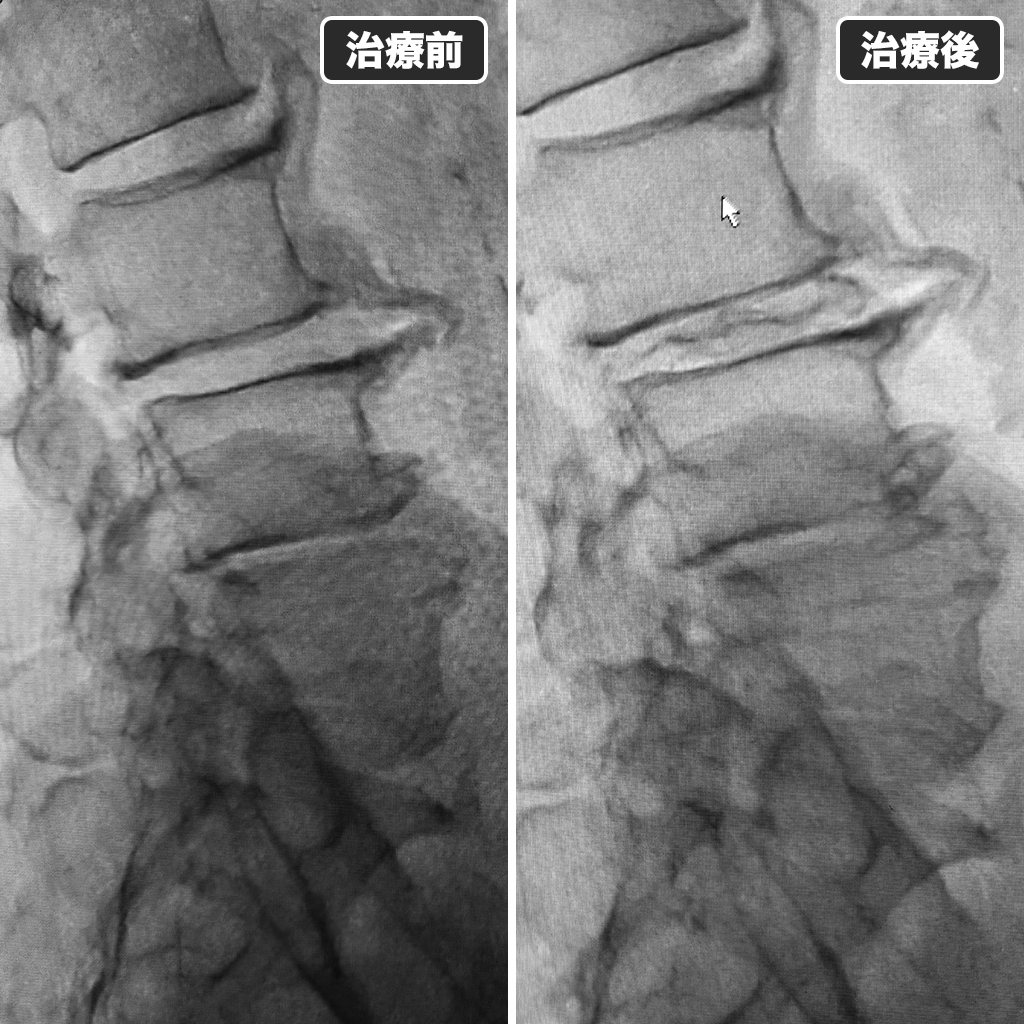

治療前後のレントゲン

治療前後のレントゲン写真です。左側が治療前、右側が治療後になります。

ゴルフの再開は1ヵ月後と念を押しました。